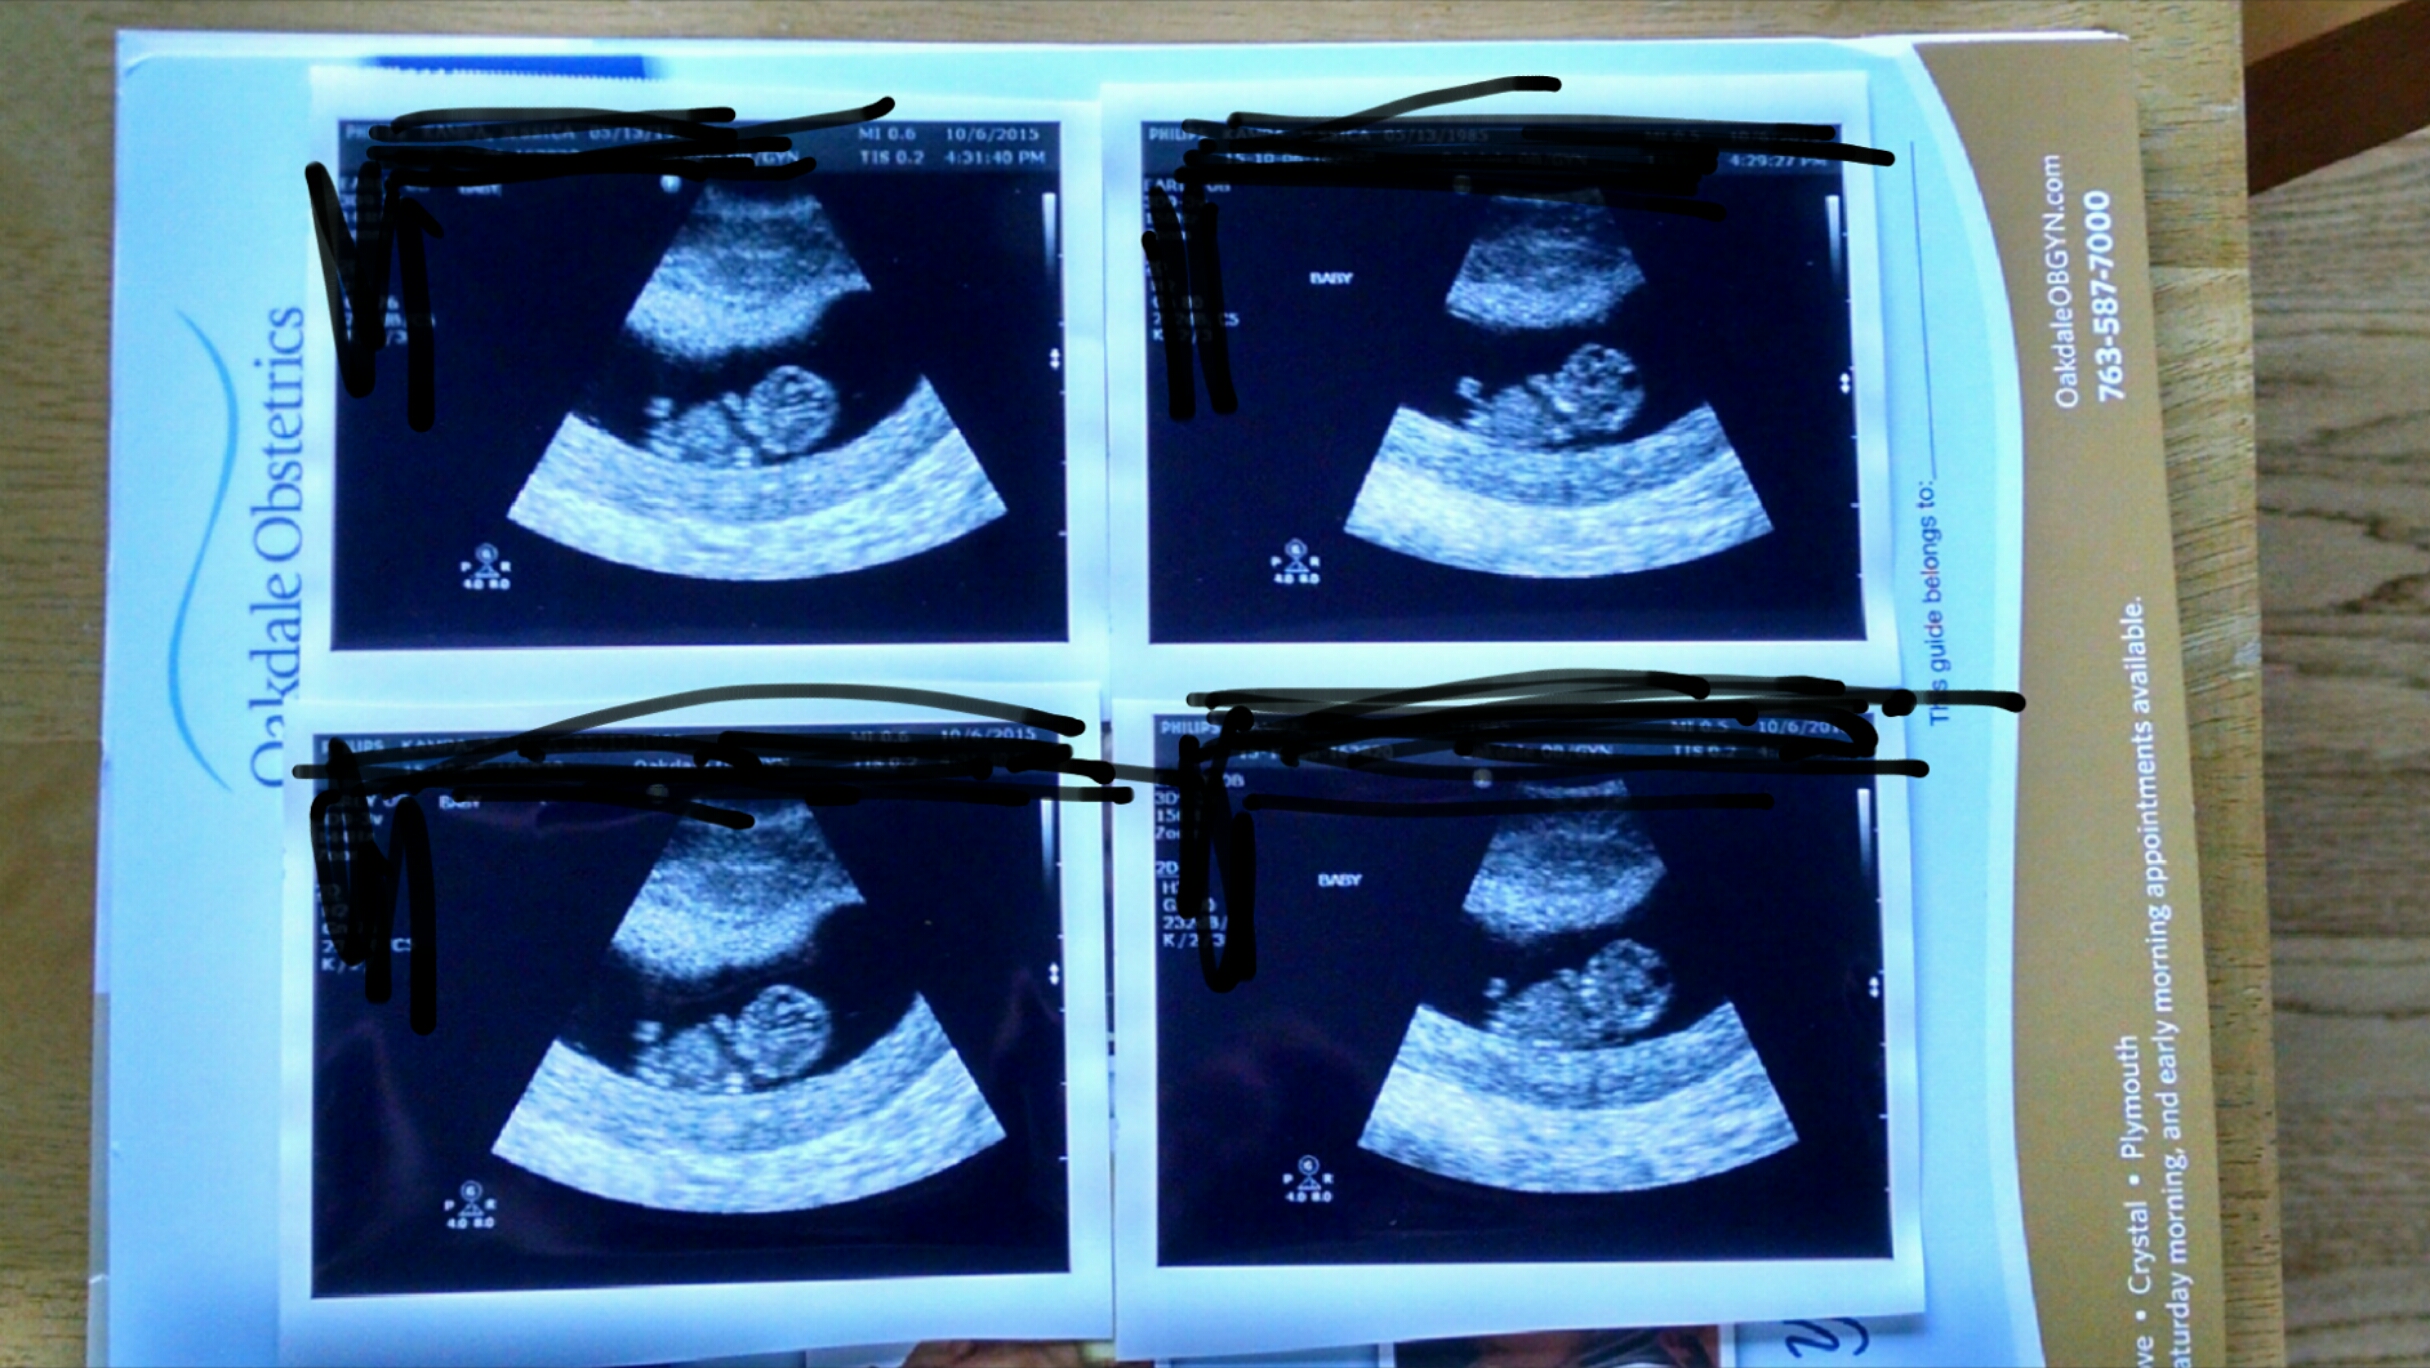

Had our first appointment yesterday. Baby measured right on track at 9w1d with a due date of May 10th! Very grateful that everything is going well so far.

Im 8wks today and went for my first ever ultrasound after 2 mc. It was great. I was measuring around 9wks though, which is also a plus! We got to hear the strong heart beat and see it wiggle around! It is just so amazingwhat our bodies do!

Had my first appointment yesterday and got to meat Bean! (That's what the husband and I call the baby!) We even heard a strong heartbeat!! Today makes 8 weeks!!! Very excited as this is our first!